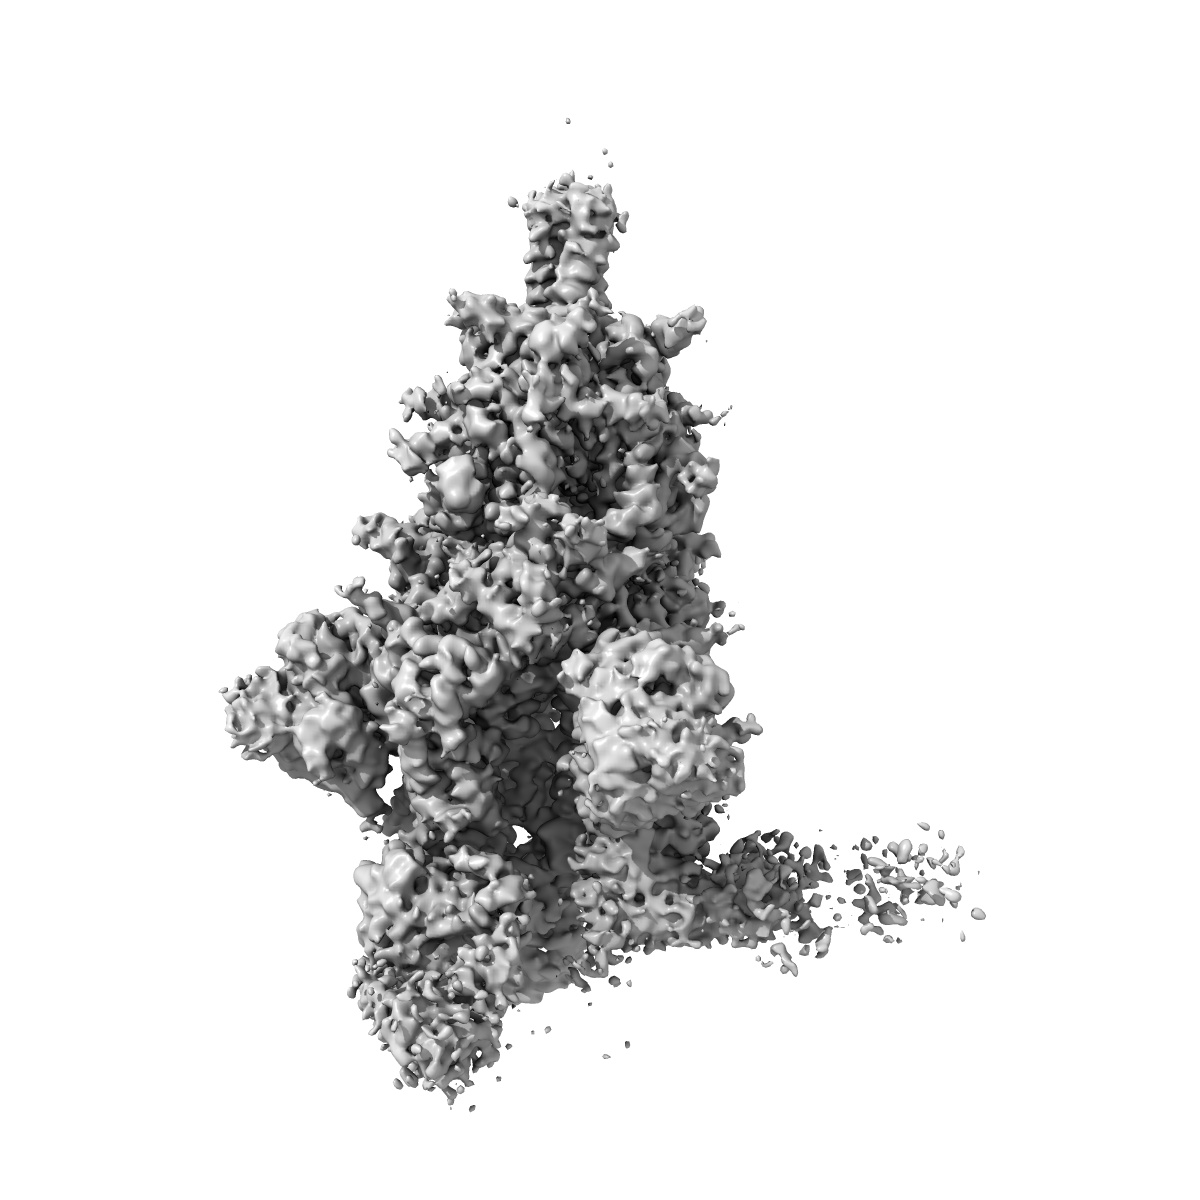

Structures of Omicron Spike complexes illuminate broad-spectrum neutralizing antibody development

Single-particle3.7 Å

Sample: SARS-CoV-2 Omicron spike glycoprotein complex with 510A5 Fab